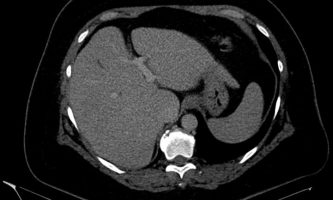

El médico de referencia le indica nueva ecografía de control, donde se observan múltiples y extensas lesiones focales hepáticas hiperecogénicas, redondeadas y confluentes, las cuales predominan en adyacencia a venas supra hepáticas, sin condicionar efecto de masa y sin alteración de la superficie hepática(fig. 1 y 2). Ante la valoración con Doppler color no presenta patrón de flujo peri ni intralesional y respeta el calibre de las venas supra hepáticas(fig. 3 y 4). Dada las características ecográficas se sospecha esteatosis focal multinodular confluente como principal diagnóstico presuntivo, siendo los diagnósticos diferenciales patologías de naturaleza infecciosa, tumoral o metastásica.

El estudio se complemento con resonancia magnética, donde se demostró la presencia de múltiples imágenes focales hepáticas confluentes con disminución de la señal en secuencias fuera de fase, no mostrando alteración de la señal en secuencias potenciadas en T2, sin signos de restricción al pulso difusión ni refuerzos anómalos luego de la administración de contraste endovenoso, estos hallazgos confirman la sospecha de esteatosis focal multinodular (fig. 5, 6 y 7).